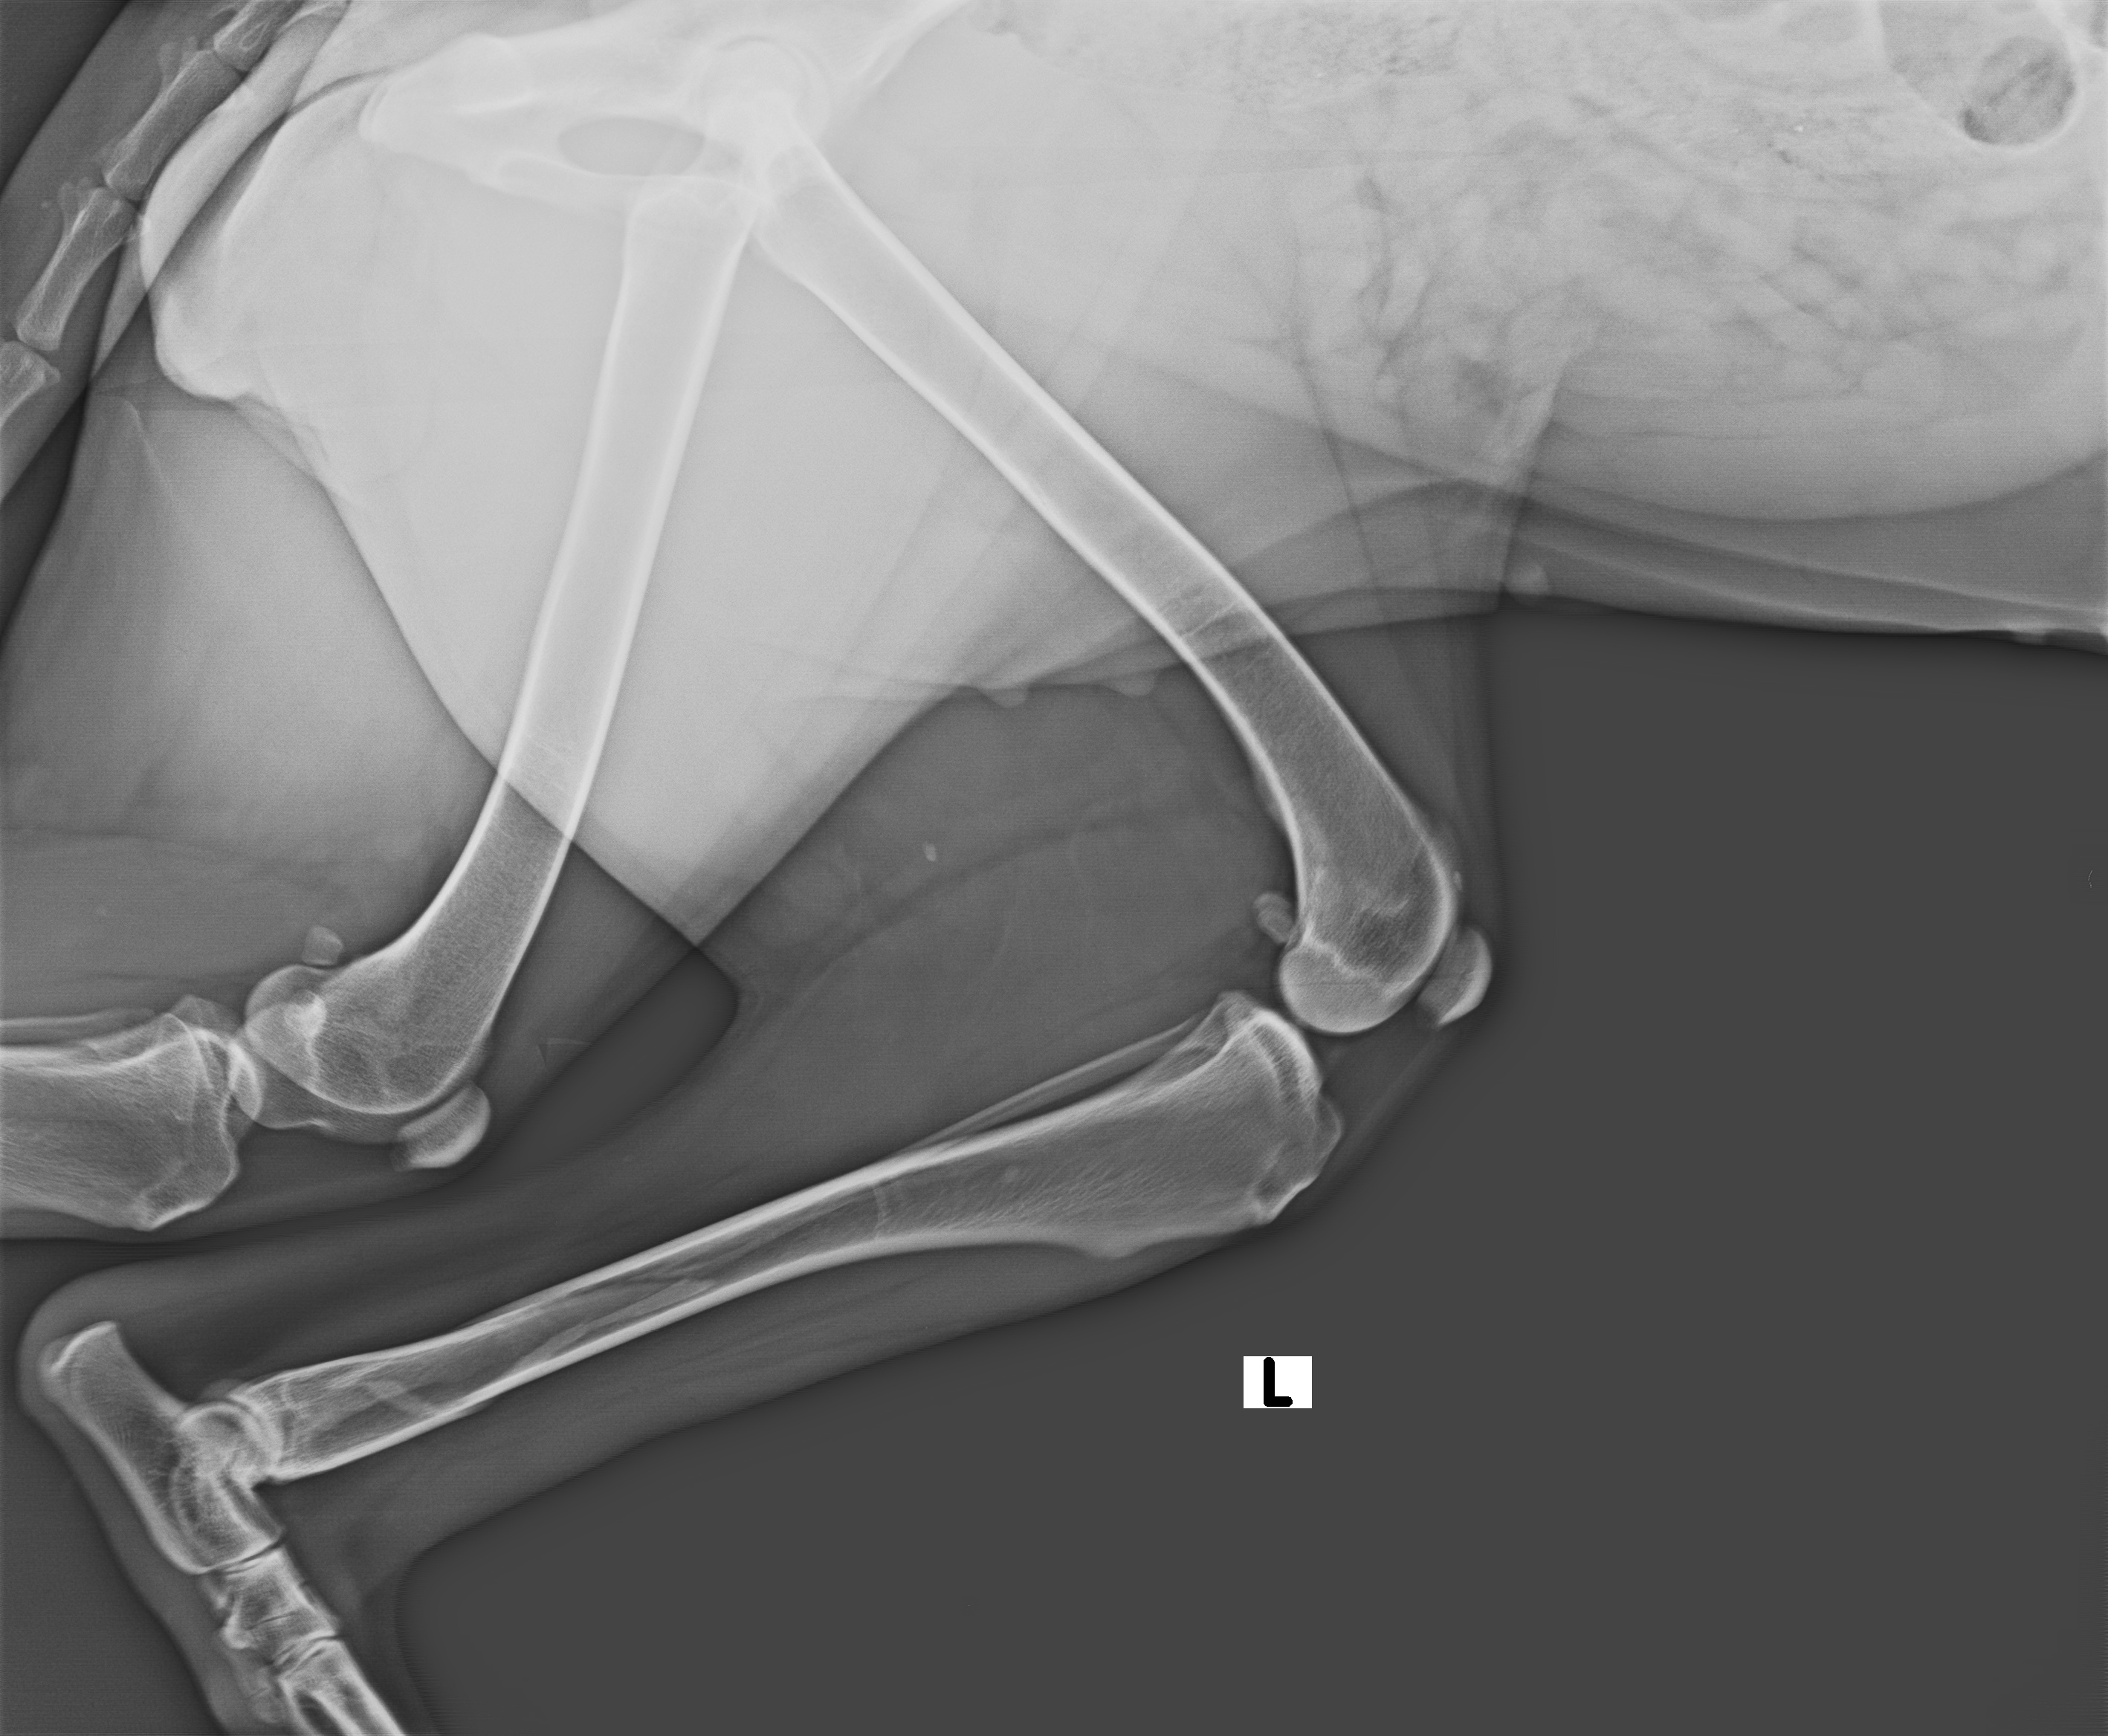

Owner's Complaint : Animal got hit by a lorry near peroorkada junction, bleeding from legs

Purpose of Visit: Treatment | Animal present : YES | Emergency : YES | Accident : YESGeen Indicates normal range | Red indicates abnormal

Images / Radiology

X-RAY

Date | 12-06-2022 | Radiologist | Name of radiologist |

Description Lorem Ipsum is simply dummy text of the printing and typesetting industry. Lorem Ipsum has been the industry's stan |

Observation Lorem Ipsum is simply dummy text of the printing and typesetting industry. Lorem Ipsum has been the industry's stan |